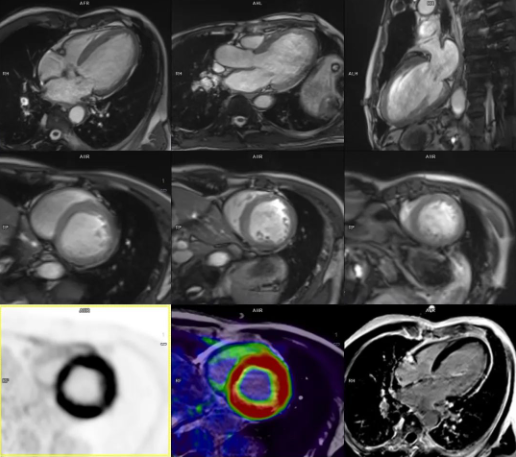

③在心血管疾病診斷方面,一體化PET / MR通過多參數、多序列成像可清晰顯示心肌解剖結構、運動功能、血流灌注和組織特性,通過MRI序列對PET圖像進行呼吸運動校正,實現時間和空間上最佳配準一站式評估,對心血管疾病診斷與治療具有重要意義。一體化PET / MR可以進行心肌灌注及心肌活力評價(圖4)、風險分層、預后、指導治療,心臟動脈硬化斑塊成像,評價瘢痕范圍(LGE)、左室功能,評價炎性心肌病及浸潤性心肌病活動狀態,心肌淀粉樣變評價。

圖4 一體化PET / MR心肌存活顯像